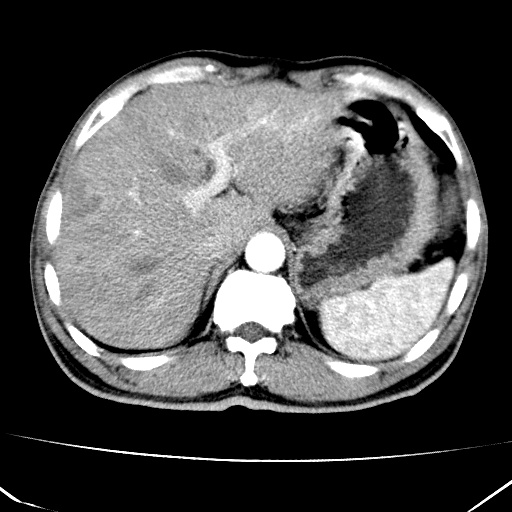

标题: CT17975:请求会诊。男、57岁。上腹部胀痛2天。临床诊断:糜 [打印本页]

标题: CT17975:请求会诊。男、57岁。上腹部胀痛2天。临床诊断:糜

肝脏多发类圆形低密度影,考虑肝脏转移瘤,肝胃韧带一淋巴结肿大,原发?胃癌?

考虑胃癌肝脏转移可能性大。

考虑胃癌并肝脏及腹膜后淋巴结转移;不排除淋巴瘤。

肝内转移瘤,腹腔及腹膜后淋巴结转移。